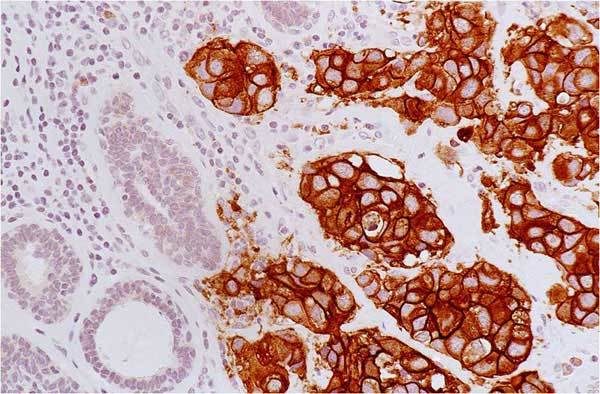

A type of laboratory test that can detect the proteins expressed by a cell. The test uses special antibodies (“immunostains”) that each binds to a particular protein in question; the immunostain will change the color of the tissue to show whether a protein is present. Examples include immunohistochemistry to look for HER-2 overexpression, as well as the expression of the estrogen receptor (ER) and progesterone receptor (PR) in breast cancer cells.

A protein called a tyrosine kinase that is expressed on the surface of all cells and helps signal for the cells to grow. Some cancers overexpress HER-2/neu on their surface, that is, they have more copies of the gene and thus protein than normal; these are called “HER-2 positive” tumors. This HER-2 overexpression allows the cells to grow abnormally. There are several types of drugs that directly target the HER-2 protein on cancer cells; one example is trastuzumab.

A laboratory test that can be used to look for HER-2/neu gene amplification in breast cancers. This test uses a probe molecule that has an attached fluorescent tag; when the HER-2/neu gene is present, the probe binds to the gene and shines brightly. The number of genes can be counted using a special fluorescent light microscope.